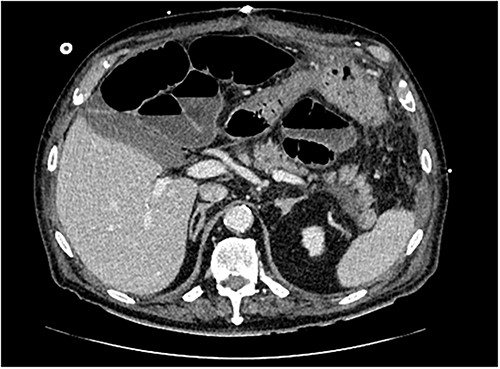

The post-operative course was initially uncomplicated, however, the patient developed new onset atrial fibrillation and fever on Day 3. A computed tomography (CT) of abdomen/pelvis demonstrated post-operative ileus without evidence of infection. Total parenteral nutrition was commenced. Due to worsening upper abdominal pain and failure to clinically progress, additional biochemical testing on Day 8 revealed a lipase of 3363 units/litre. A repeat CT of the abdomen/pelvis demonstrated mild peripancreatic fluid without evidence of necrosis along with persistent post-operative ileus (Fig. 2). An ultrasound (US) revealed cholelithiasis with evidence of cholecystitis or choledocholithiasis. Conservative management of AP with analgesia, fluids and electrolytes was initiated.

Transverse section of CT abdomen/pelvis performed on post-operative day 8, illustrating peripancreatic fluid and post-operative ileus.